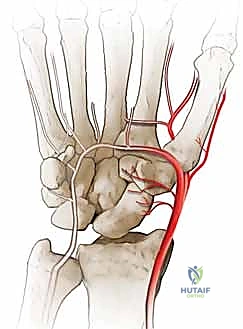

المشكلة الكبرى التي تواجه العظم الزورقي تكمن في التروية الدموية (Blood Supply). الدم يدخل إلى العظم الزورقي من الجزء البعيد (Distal pole) ويتجه نحو الجزء القريب (Proximal pole) في اتجاه عكسي (Retrograde). لذلك، عند حدوث كسر في منتصف العظم، ينقطع الدم عن الجزء القريب، مما يؤدي إلى عدم التئام الكسر (Nonunion) وفي كثير من الأحيان موت العظم (Avascular Necrosis).

هذه الحركة غير الطبيعية تخلق احتكاكاً مستمراً (Micro-trauma) مع العظام المجاورة، وتحديداً عظم الكعبرة (Radius). بمرور الوقت (أشهر أو سنوات)، يؤدي هذا الاحتكاك إلى تآكل الغضاريف الناعمة التي تغطي العظام، مما يسبب خشونة مفصلية شديدة (Osteoarthritis).